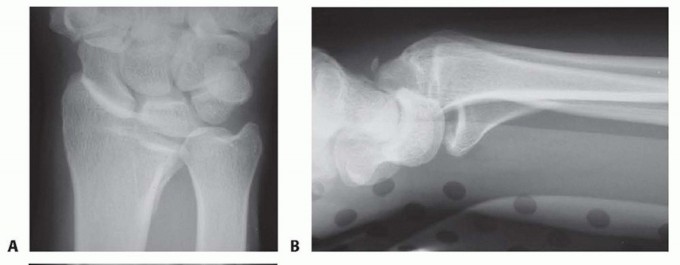

FIG 2 • Articular fracture components.

Structurally, the wrist can be thought of in terms of three basic support columns: a radial column that includes the radial border of the distal radius and scaphoid facet, a middle column consisting of the central and ulnar part of the radial shaft and lunate facet, and an ulnar column that includes the DRUJ, the triangular fibrocartilage complex (TFCC), and the ulnar head.The radial column fragment involves the pillar of bone along the radial border of the distal radius ( FIG 2). Restoration of radial length is important to correct the axial position of the carpus, unloading deforming compressive forces that can interfere with reduction of middle column injuries. Typically, the terminal portion of the brachioradialis inserts on the base of the radial column fragment and may be a deforming force that contributes to proximal displacement of the radial column fragment. Metaphyseal comminution along the base of the radial column fragment may also contribute to radial column instability. Although not common, radial column injuries with secondary coronal fracture page or segmental comminution into the shaft proximally can be particularly unstable fracture patterns.The volar rim of the lunate facet is a primary load-bearing structure of the articular surface. Instability of the volar rim occurs in two patterns:In the volar instability pattern, the volar rim migrates in a proximal and volar direction resulting in secondary palmar translation of the carpus.In the axial instability pattern of the volar rim, axial impaction of the carpus drives the volar rim into dorsiflexion, resulting in secondary axial and dorsal subluxation of the carpus.The ulnar corner fragment involves the dorsal half of the sigmoid notch and usually includes a small dorsal ulnar corner of the articular surface of the lunate facet. This fracture component is the result of impaction of the lunate into the articular surface, causing the fragment to migrate dorsally and shorten proximally. Residual displacement of the ulnar corner may result in instability of the DRUJ as well as restriction of forearm rotation.Dorsal wall fragmentation may be a typical finding in either dorsal bending or axial loading injuries. If displaced, this fracture component is often associated with dorsal subluxation of the carpus in addition to the typical dorsal angulation of the articular surface.Free articular fragments may be impacted within the metaphyseal cavity and result in incongruity of the articular surface. Elevation of dorsal wall fragments allows direct access to reduction of free articular fragments.